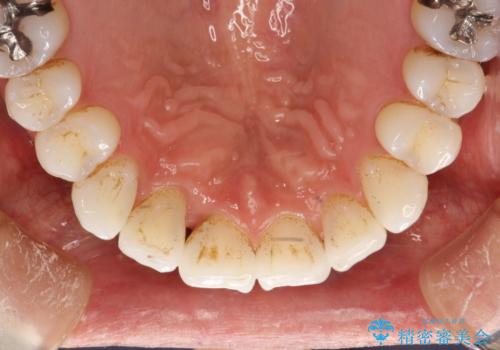

インビザライン終了時のPMTC

- インビザライン治療が終了し、アタッチメント除去の際にクリーニング(PMTC)も希望されました。

PMTC60分1万円+tax(保険適応外)を行いました。

インビザライン矯正治療は、歯にアタッチメント(歯を動かすための突起物)をつけます。そのため、矯正治療が終了し、アタッチメントを外すと着色が目立つことがあります。矯正治療の終了のタイミングではクリーニングを行い、着色の除去や歯と歯の間・歯と歯肉との境目などのケアをしっかりすることをおすすめしています。